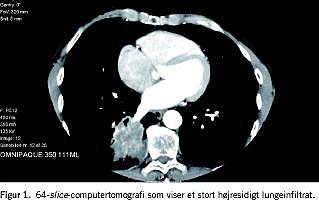

En 60-årig mand med atypiske brystsmerter og intermediær sandsynlighed for iskæmisk hjertesygdom. Ved arbejdselektrokardiografi fandtes en god arbejdskapacitet, patienten var asymptomatisk, men efter arbejdstesten opstod horisontalt forløbende ST-depressioner i de prækordiale afledninger. Ved hjerte-CT fandtes arteriosklerotiske plaques svarende til såvel de venstre- som højresidige koronarkar. Som bifund fandtes et højresidigt malignt udseende lungeinfiltrat; efterfølgende konventionel computertomografi af thorax og abdomen bekræftede en seks cm stor tumor i højre lunges underlap med metastasesuspekte lymfeknuder i mediastinum (Figur 1 ). Histologisvaret viste adenokarcinom med metastaser til lymfeknuder i mediastinum og paraaortalt.